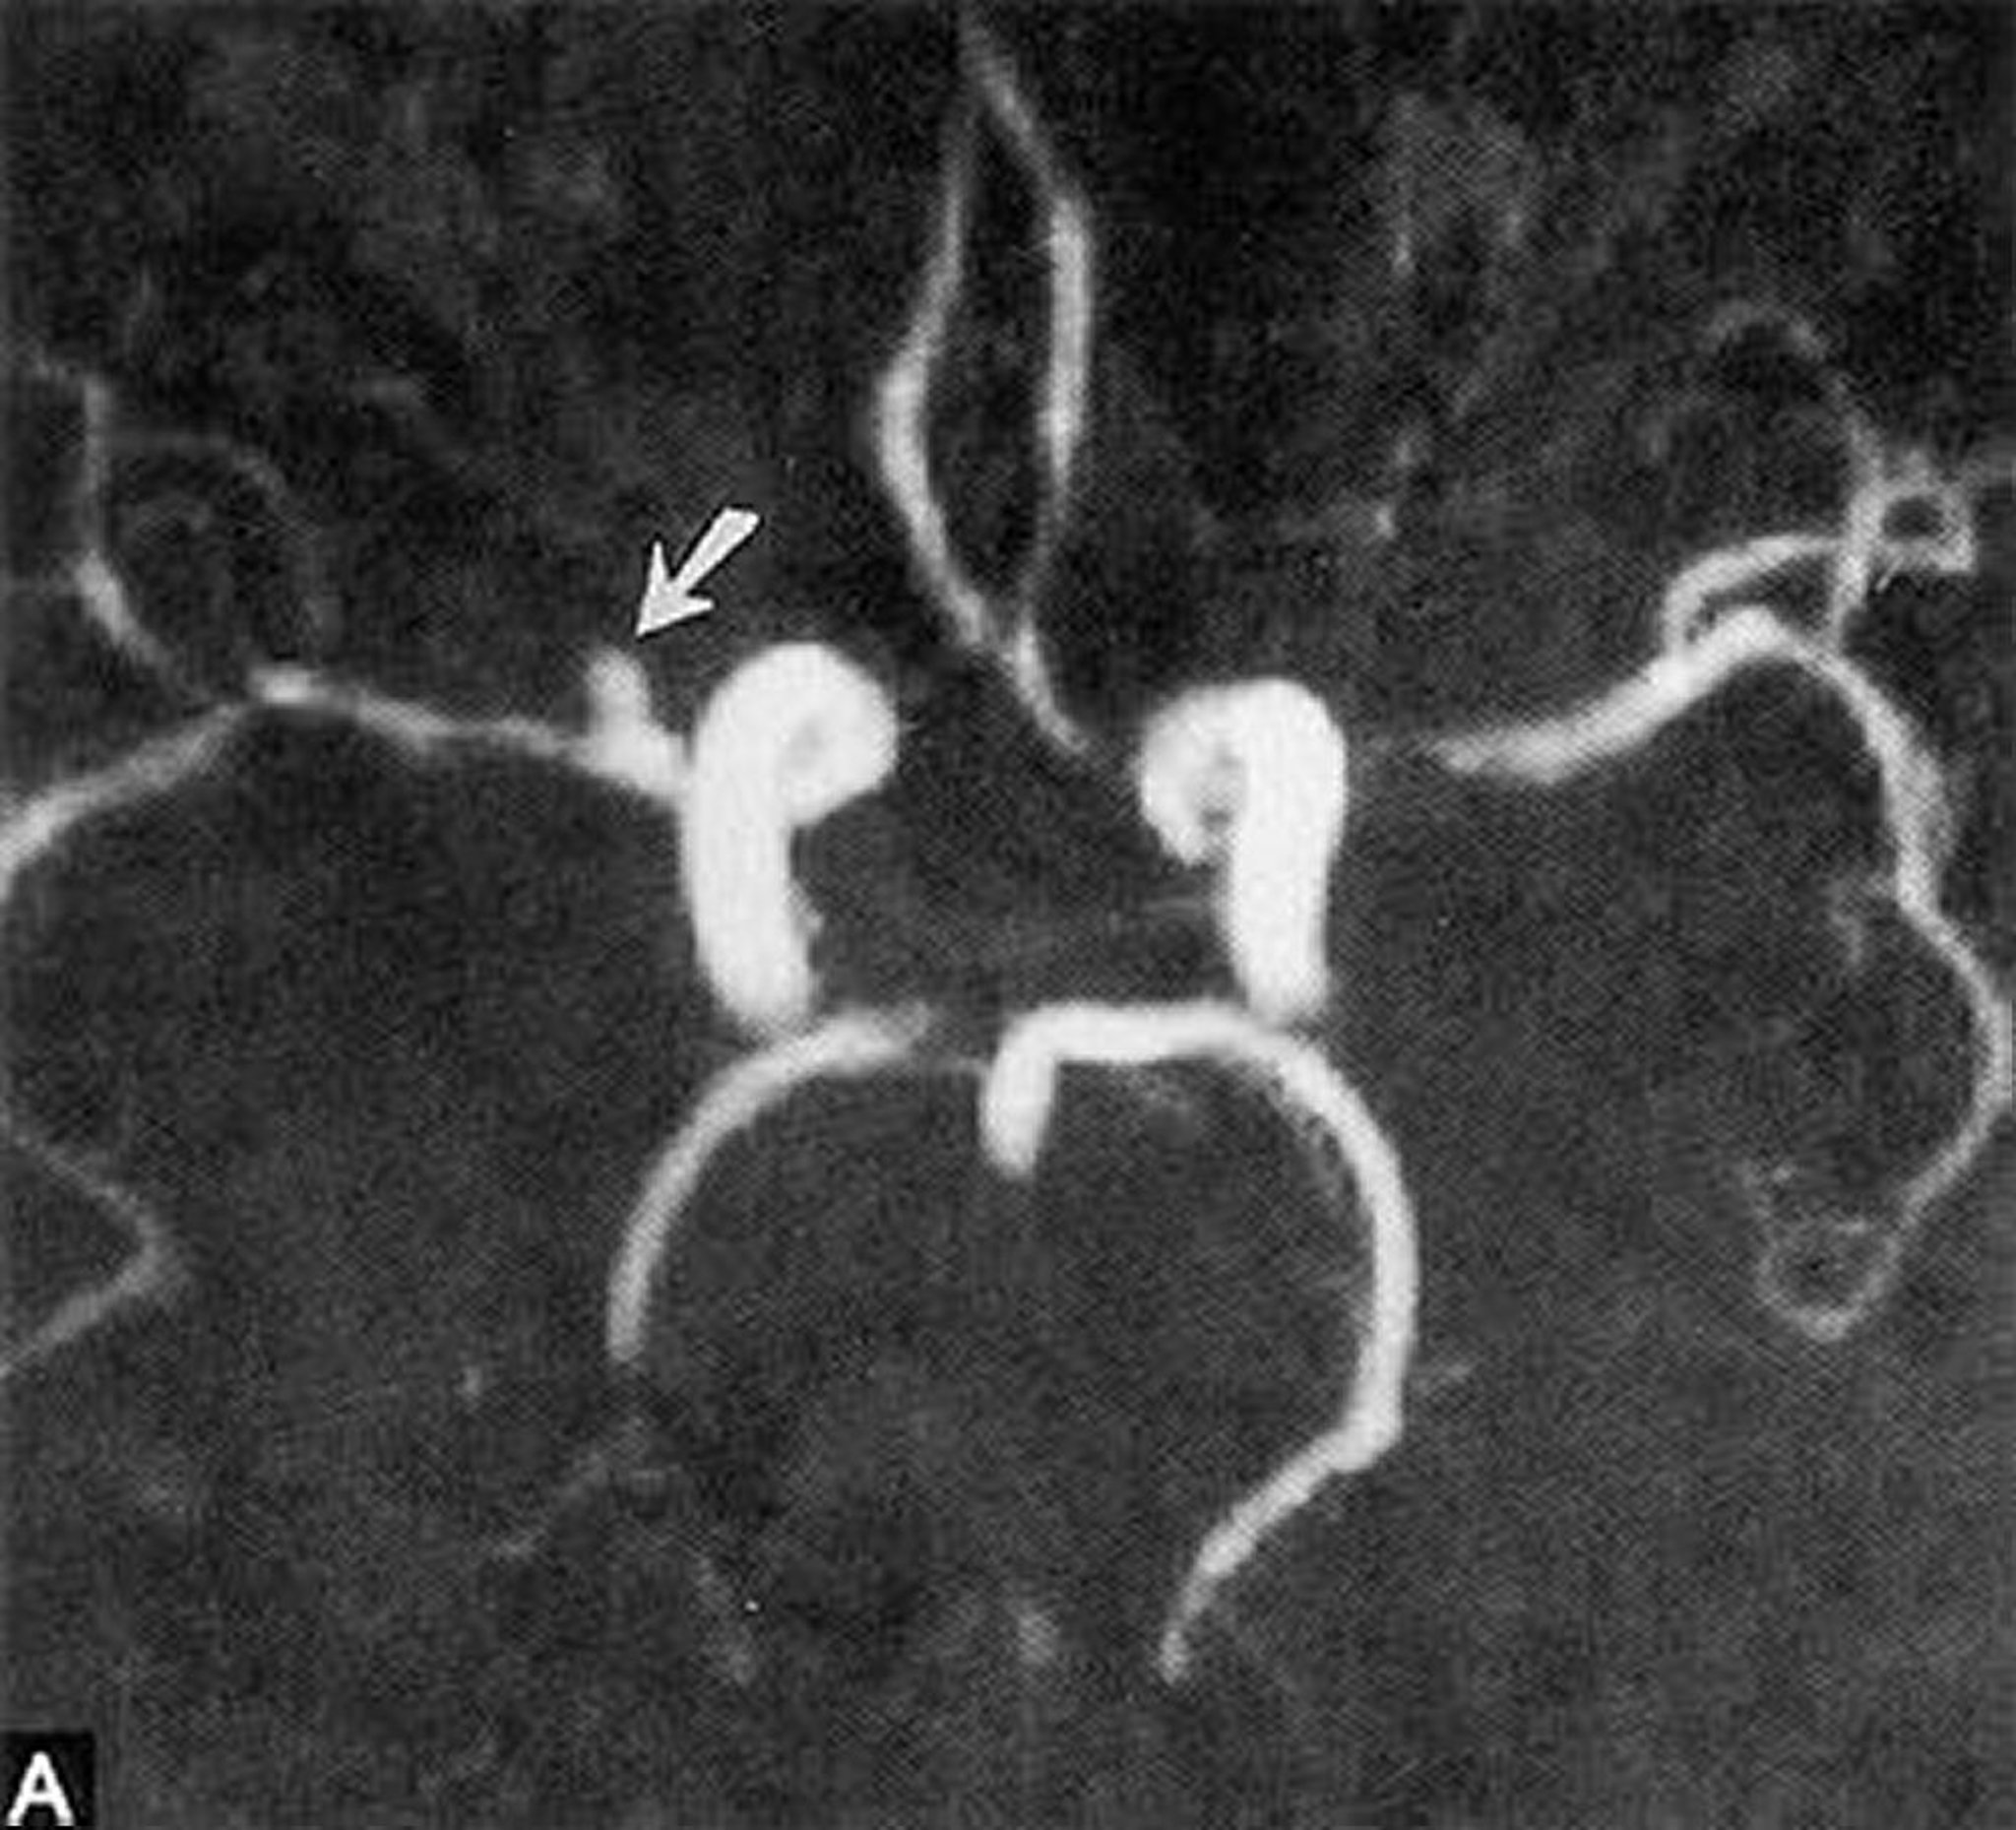

Diagnosis of aneurysms requires angiography, CT angiography, or magnetic resonance angiography. Catheter-based digital subtraction angiography (DSA) is the gold standard for diagnosing aneurysms. When initial CT angiography or DSA is negative for an aneurysm in patients with subarachnoid hemorrhage around the circle of Willis, delayed DSA performed 7 days after the initial aneurysmal bleeding is valuable.

By permission of the publisher. From Ritter A, Hayman L, Charletta D. In Atlas of Cerebrovascular Disease. Edited by PB Gorelick and MA Sloan. Philadelphia, Current Medicine, 1996.